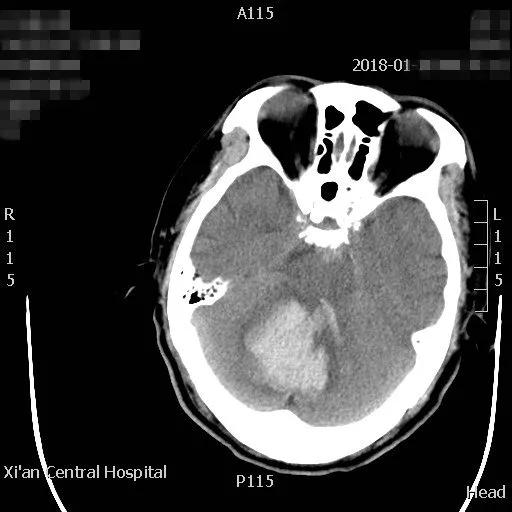

近日,一位六十岁的男性,在家中突发头痛、呕吐、左侧肢体瘫软无力摔倒在地,被家人急送21点玩法研究所 急诊科,急诊接诊后发现患者处于昏迷状态,遂急查颅脑CT并请神经外科会诊。CT结果显示患者小脑出血40毫升,即刻收住神经外科住院。

患者病情危重,出血点位于后颅窝靠近天幕,位置狭小、深在、靠近脑干、直视困难,应用普通手术操作困难,容易损伤脑干,血肿也不容易彻底清除。主管主任医师王占尧对该患者进行了详细的查体后,与治疗小组商议手术方案。为进一步减少小脑皮层损伤、降低颅脑创伤,王占尧主任医师决定对该患者使用内镜辅助清除血肿。